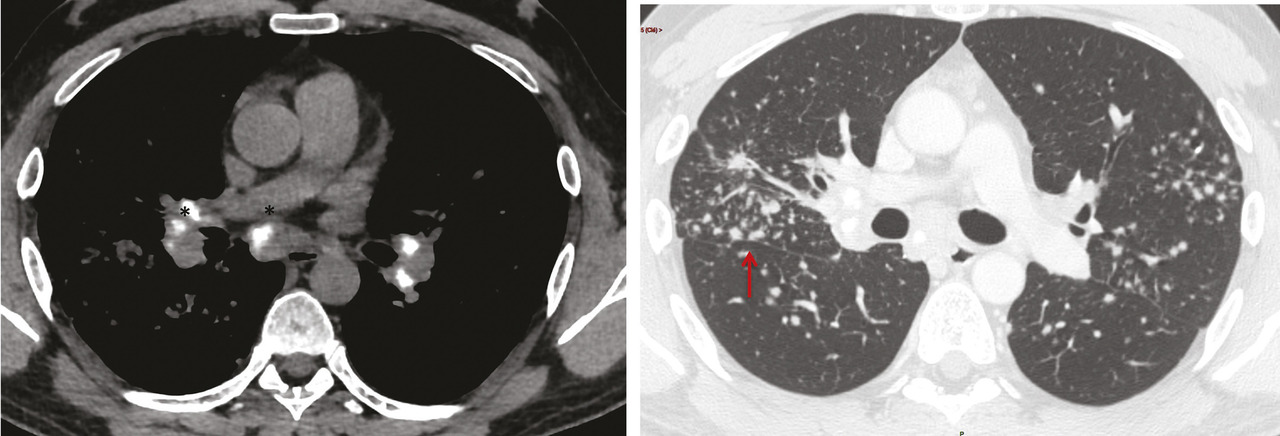

La tomodensitométrie thoracique a un grand intérêt diagnostique surtout en cas de présentation peu typique. Le tableau typique32 (fig. 2) est celui de l’association d’adénopathies médiastino-hilaires bilatérales et symétriques associées à des micronodules de distribution périlymphatique (les micronodules suivent les trajets lymphatiques et se retrouvent le long des axes péribronchovasculaires, à l’échelle du lobule secondaire dans les septums interlobulaires, en sous-pleural et notamment le long des scissures) prédominant dans les territoires supérieurs et moyens (fig. 3). Ce tableau permet de prédire avec plus de 95 % de sécurité un diagnostic de sarcoïdose chez 80 % des patients.2, 33, 34 Dans les rares cas où des lésions non habituelles prédominent, comme le verre dépoli ou les condensations, la présence d’adénopathies typiques ou de micronodules périlymphatiques même au second plan permet dans la plupart des cas de retenir le diagnostic de sarcoïdose.35, 36 La tomodensitométrie permet, en outre, de renseigner avec plus de précision sur le caractère réversible inflammatoire (micronodules, nodules) ou irréversible des lésions (fibrose). Les lésions de fibrose pulmonaire prédominent dans les territoires supérieurs moyens et périhilaires. Le tableau le plus typique est celui de réticulations avec distorsion péribronchovasculaire prédominant dans les lobes supérieurs dont le volume est réduit. Des adéno- athies calcifiées bilatérales peuvent témoigner de la déclaration ancienne de la maladie.37